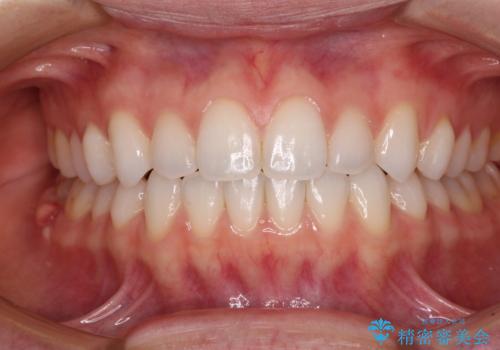

上下前歯が接触しない オープンバイトをインビザラインで改善

- 10ヶ月

上下の奥歯を圧下させるようにすることで、前歯を接触させるように計画しました。

上下の隙間に舌が入り込むことがオープンバイトの原因であったため、舌の筋肉のトレーニングも並行して行い、後戻りの抑制を図りました。